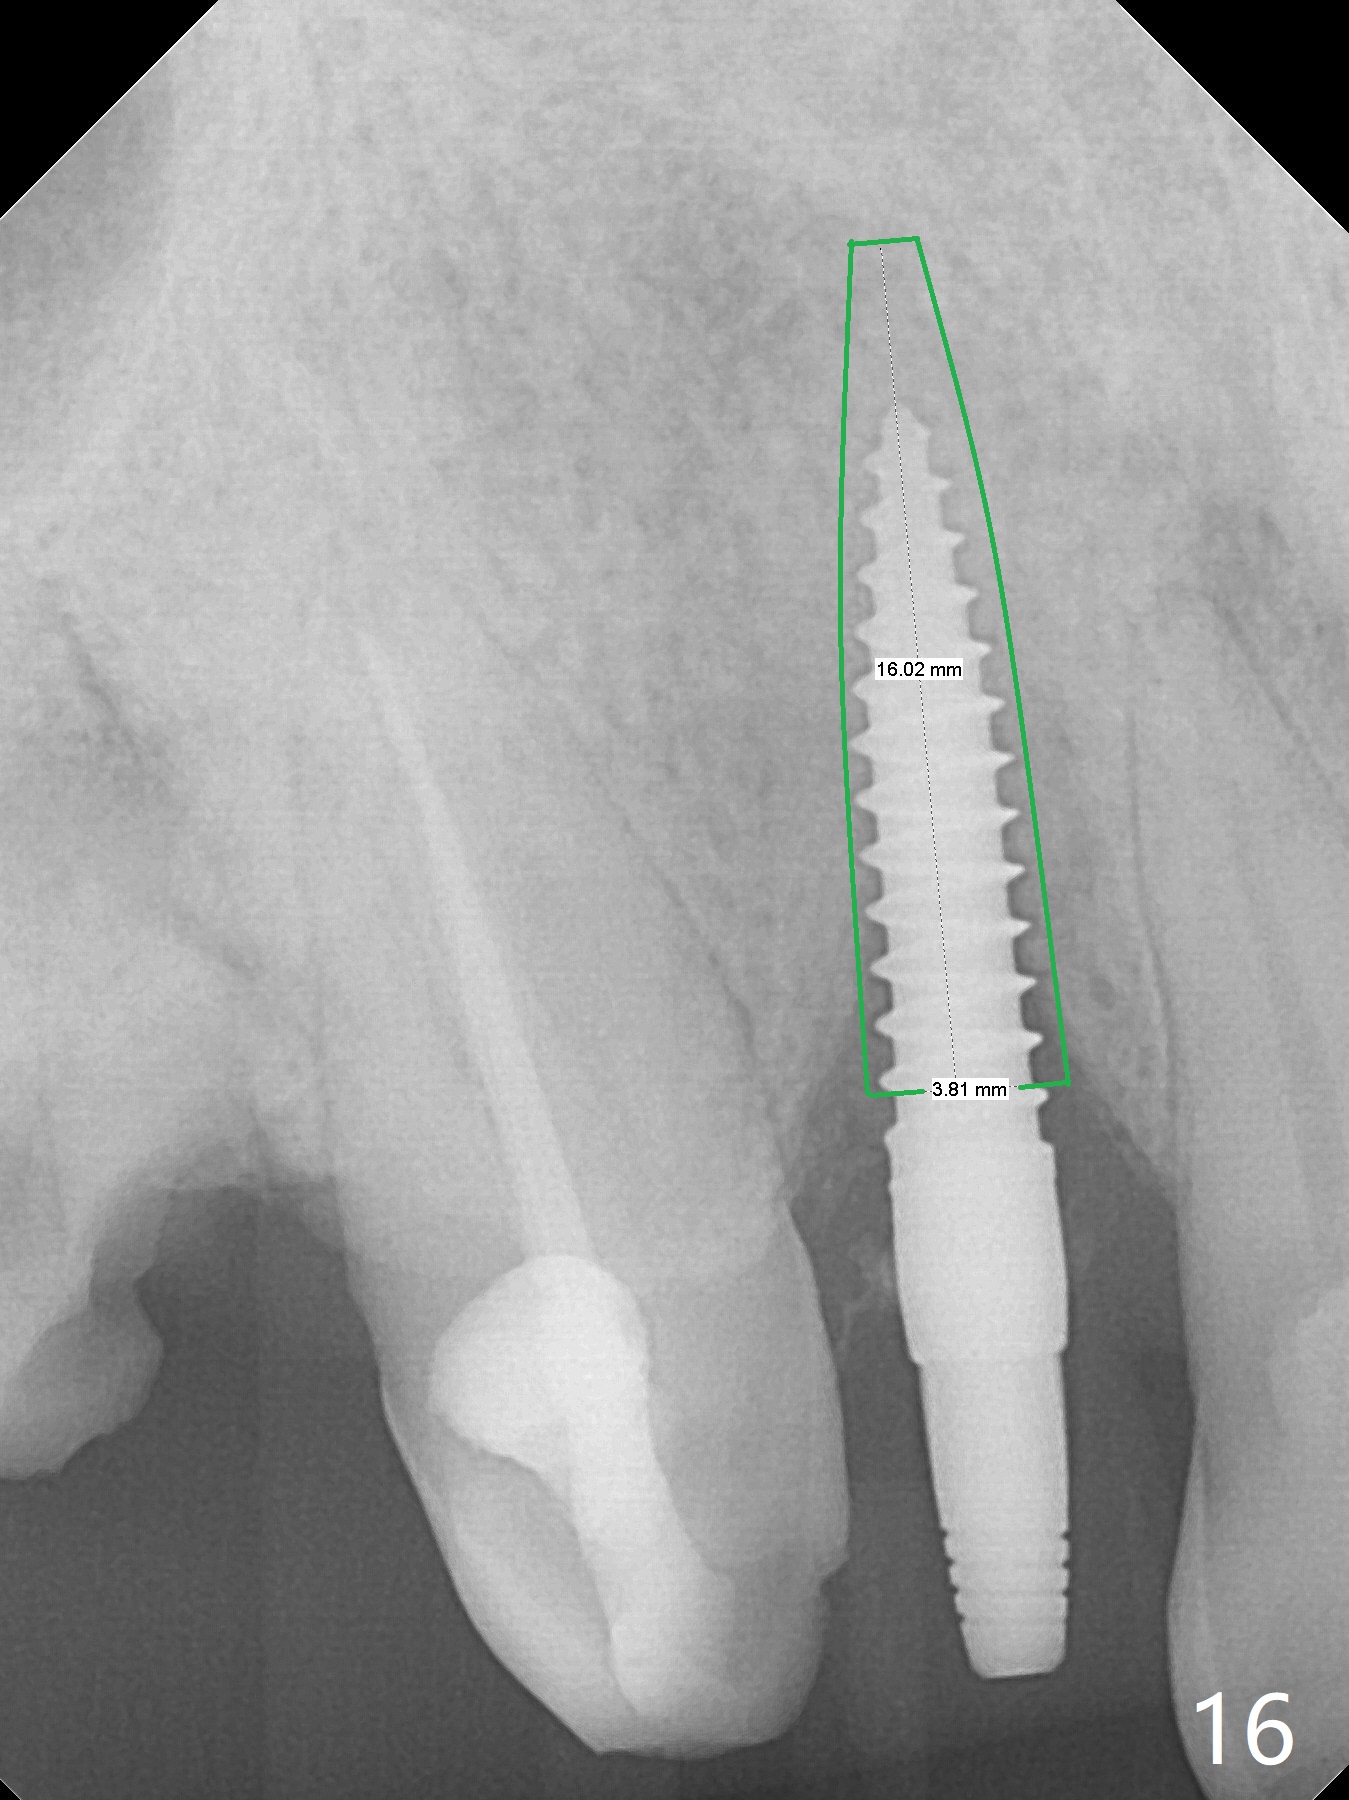

An apical abscess is present when the patient returns for immediate implant at #7 (Fig.1 *); a 2nd challenge is deep bite. After smooth extraction, the apical buccal plate is found to be perforated. Following debridement, a piece of gauze is placed in the apical defect for hemostasis, while osteotomy is initiated palatal (Fig.2). The apical defect seems to be extensive (Fig.3 yellow dashed line). A new trajectory is intended (red arrow) without much success. Before implant placement, bone graft is placed in the apical defect defect area, while a drill (Fig.4 D) is inserted in the finished osteotomy (Fig.5 O). In spite of seemingly large apical defect, the buccal crest bone exists (Fig.4 x). A 3x14(2) mm 1-piece implant is placed with stability; the first round of bone graft is apparently around the apical portion of the implant (Fig.6 *). The coronal end of the implant has to be adjusted several times buccopalatally to accommodate the deep bite. A 2nd round of bone graft following an immediate provisional closes the coronal space of the socket (Fig.7 *). CT will be taken to show the bone graft to repair the buccal plate defect when the patient returns for postop follow-up. In fact the defect is minimal in CT a month ago. The fistula does not disappear 1 week postop, but it is non tender (Fig.8). The patient complains of asymptomatic swelling in the right nostril. CT shows that the large buccal perforation is repaired with large amount of bone graft (Fig.9,10 *). It would be nicer to place the implant slightly more buccal apically (Fig.11 red lines; Fig.12 (preop design)). The buccoapical fistula disappears nearly 1 month postop (Fig.13). The apparently "lifeless" bone graft seems to be harmonious with the surrounding tissue (Fig.14). The periimplant gap reopens with implant mobility nearly 4 months postop (Fig.15), which is related to micro-movement associated with the immediate provisional. The latter is removed. A larger 2-piece implant will be placed in a 2-staged manner if needed (Fig.16). In fact the 3x14 mm straight 1-piece implant (Fig.17) has no mobility when it is retightened, but the trajectory remains buccal. Incision shows that there is no implant thread exposure. A 3x14 mm 15 degree angled 1-piece dummy implant is able to establish the correct trajectory, but there is no occlusal clearance (Fig.18). Micromovement during osteointegration may recreate loosening. Finally using Lindamann bur, the osteotomy is changed so that a 3.5x13 mm 2-piece implant does not need an angled abutment to establish occlusion (Fig.19). There is one palatal thread exposure. Allograft is placed circumferentially, followed by Human Amnion-Chorion Allograft and Collagen Plug. The wound does not heal 8 days postop (Fig.20), as related to the age (79 years old)? The wound appears to heal with a membrane on the surface (Amnion-Chorion one?) 3 weeks postop (Fig.21). The ridge looks wide 3.5 months postop (Fig.22,23). A 4.5x5.5(3) mm appears to be seated incompletely with a gap between the abutment and the implant (Fig.24<). A provisional is fabricated after heavy palatal reduction. Two months later, the provisional fractures. After repositioning the abutment with complete seating and torque (Fig.25), impression is taken. Although the buccal plate is concave, the gingiva remains healthy 10 months post cementation (Fig.26,27).